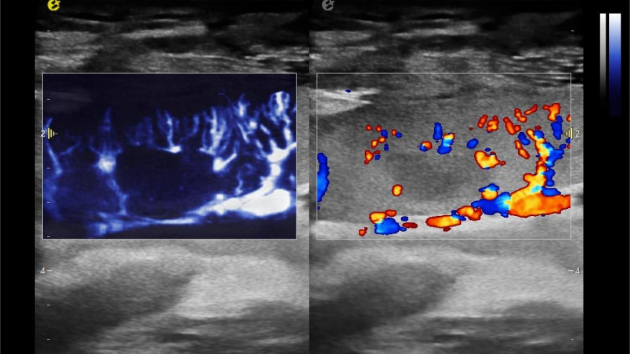

在肾移植领域,医生最怕的不是手术刀下的惊心动魄,而是那些手术后肉眼看不见的危机——急性排斥反应导致的血小板聚集形成的微血栓、毛细血管网损伤等...这些“隐形杀手”曾让无数移植肾在悄无声息中衰竭。而3377体育医疗(ESI)的iPlane Vascular平面波超微细血流显像技术,正是为破解这一难题而生。

这项革命性技术通过三大创新实现质的飞跃:

1) 基于OmniSound?平面波超快速平台,超声信号采集帧频提高了200倍(25000Hz)。

2) 可检测20-50μm级细小血管低速血流信号,能看清头发丝1/2粗细的微血管;

超微视血流显像评估肾移植术后灌注情况

这一项无创、无辐射操作简便且无需造影剂的黑科技,相当于用"高速摄像机"记录血液细胞的运动轨迹,让血管并发症"无处遁形。